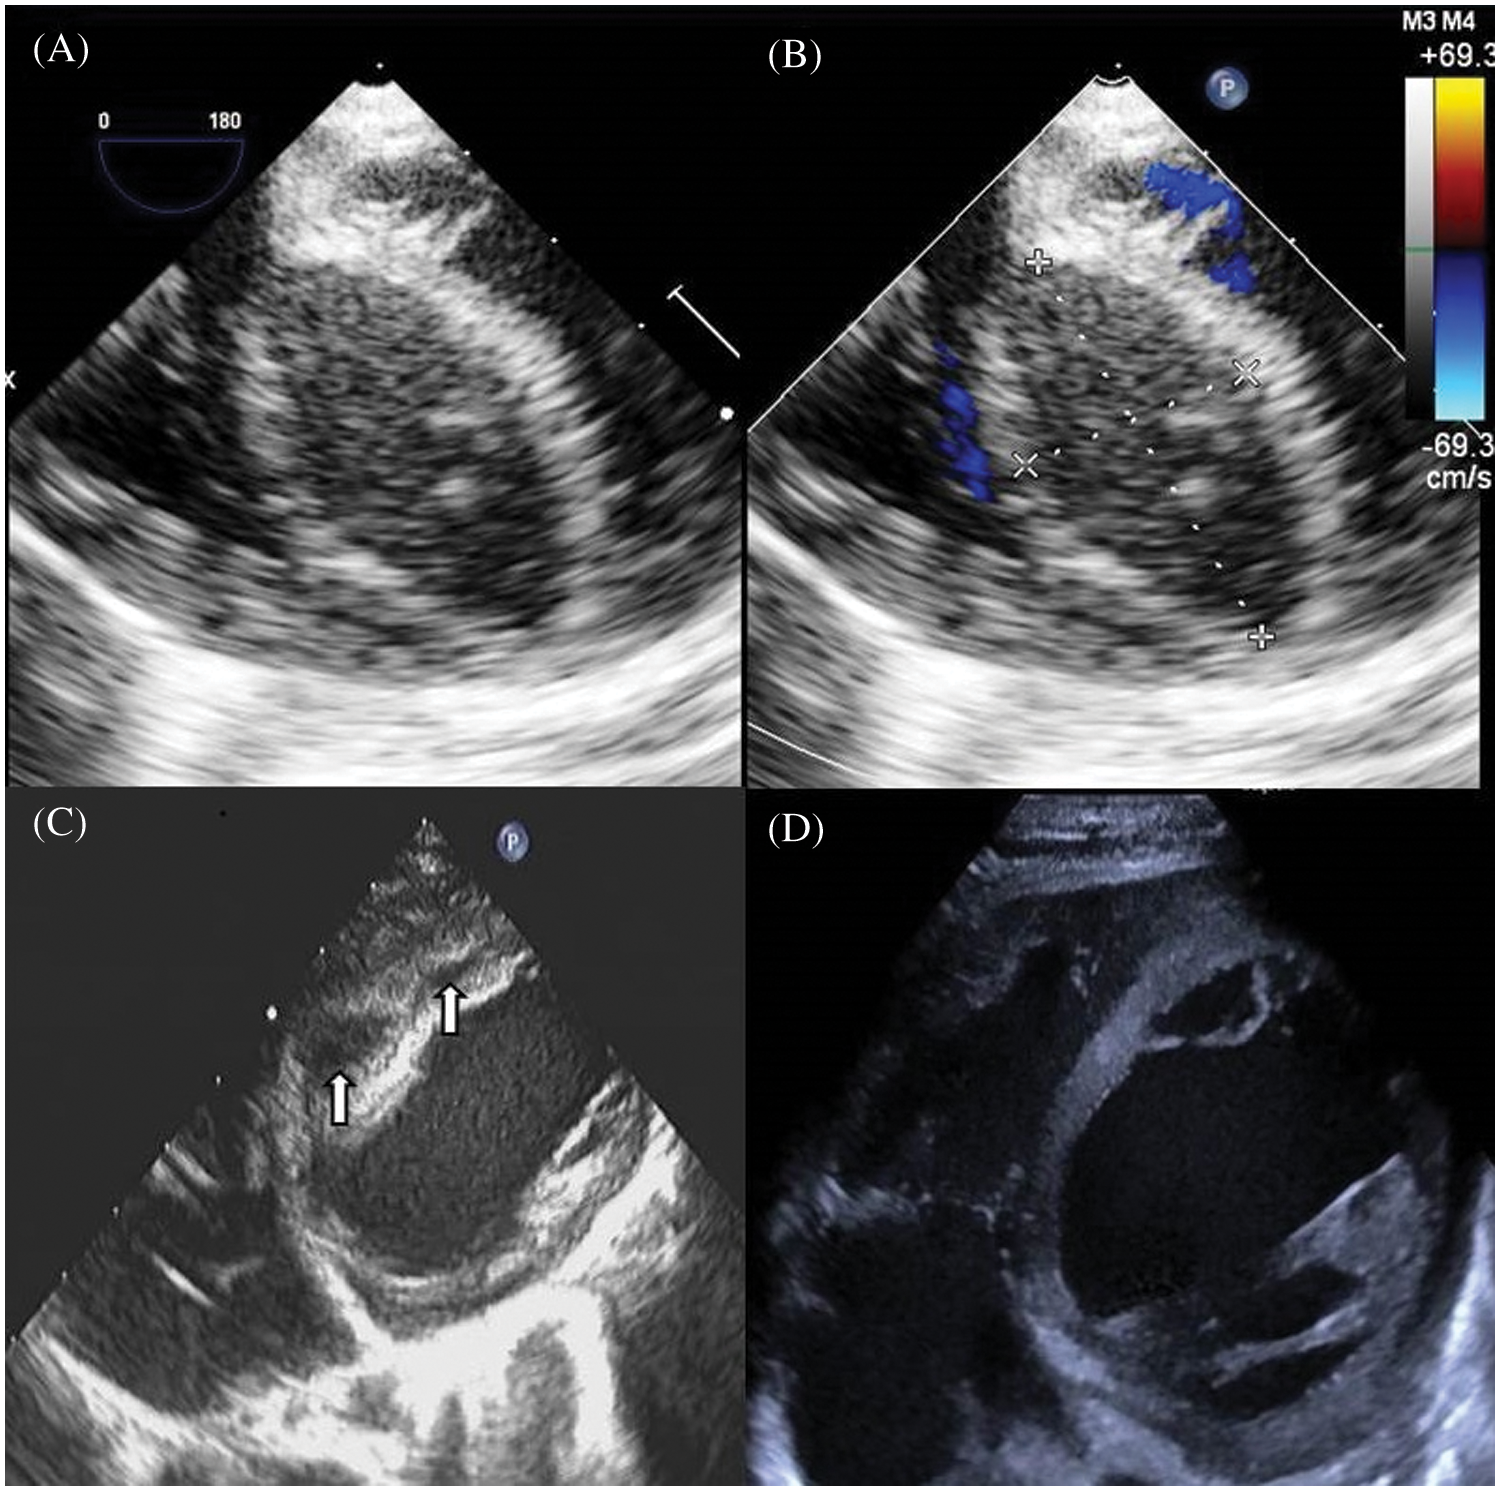

The thickness of the ventricular septum was normal before cardiopulmonary bypass in all the 5 cases. There was no residual shunt around the ventricular septal patch postoperatively. Postoperative TEE monitoring of the interventricular septum typically showed a fusiform thickening, mostly located in the middle of the ventricular septum at the lower end of the patch (range: 11 mm × 6 mm–40 mm × 29 mm in maximum as shown in echocardiographic views). Mixed echoic areas dominated by hypoechoic areas could be seen inside, with irregular borders and no visible ventricular cavity connected (Fig. 1). In one case with DORV, a similar mixed echoic area was found in the free wall of the right ventricle, with a hypoechoic area predominantly connected to the mixed echoic area of the interventricular septum. The right ventricular outflow tract was compressed and narrowed. The ejection fractions were normal in three, moderately impaired in one and severely impaired in the last one.

Figure 1: Echocardiographic views of an infant presenting with an interventricular septal hematoma after VSD repair. (A) TEE (four-chamber view) image demonstrates a large interventricular septal hypoechoic hematoma measuring 36 mm × 18 mm, with clear boundary. (B) Color Doppler shows no visible blood flow signal in the hematoma. (C) Ten days after surgery, TTE shows diminishing hematomas separated as two masses sized 15 mm × 9 mm, 10 mm × 4 mm, respectively, with echolucency. (D) 42 days after surgery TTE shows the thickness of the septum is normal, without echolucency

All patients were followed up regularly, typically 1 month, 3 months, 6 months and 1 year and then once a year postoperatively. 4 patients were doing well with no further hospitalization. The hematomas disappeared, and the thickness and echolucent mass of the ventricular septum returned to normal at 11–56 days (39.8 ± 16.9 days) (Figs. 1 and 2). The patient with impaired cardiac function remained to have significantly enlarged left ventricle (Z score 5.24) with a low ejection fraction of 29%. He was re-hospitalized 146 days after operative for cardiac failure and pneumonia. His NT-pro B-type natriuretic peptide, dropped from 8051.0 pg/ml right after operation to 789.8 pg/ml one year later. He is now doing basically well with no shortness of breath and is gaining weight normally. Close observation is warranted.